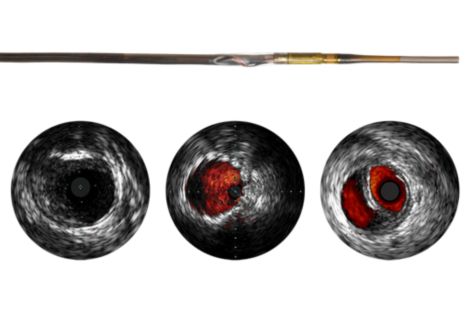

Visions PV .018

Digital IVUS Catheter

As an adjunct to conventional angiographic interventions, the Visions PV .018 digital IVUS catheter evaluates vascular morphology in blood vessels and provides cross-sectional imaging of these vessels. With a 135 cm working length and 24 mm max imaging diameter for 0.018” guide wire interventional procedures, the device aids in peripheral artery disease diagnosis and guides clinicians toward the correct therapy for the patient’s unique needs.

Digital IVUS catheter evaluates vascular morphology in blood vessels

Provides cross-sectional imaging of these vessels

135 cm working length and 24 mm max imaging diameter for 0.018” guide wire interventional procedures

• ChromaFlo provides easy assessment of lumen size and stent apposition

ChromaFlo provides easy assessment of lumen size and stent apposition

IVUS imaging helps to confirm treatment results, including the completeness of treatment, the apposition and expansion of stent placement, and whether or not the patient requires a thrombolytic drip. ChromaFlo imaging, for example, can be used to show evidence of stent apposition by illustrating the absence of flow.